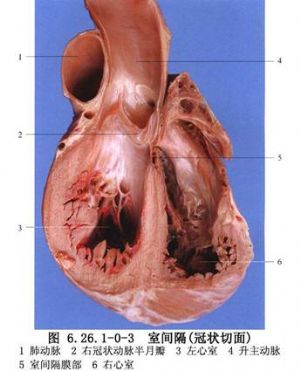

室間隔由4個部分,即膜性間隔、流入道間隔、小梁間隔、流出道間隔或漏斗部間隔組成。缺損可發生在室間隔各個部位或其交接部(圖6.26.1-0-1)。從胚胎髮育情況及分佈部位,室間隔缺損可分爲膜部間隔或膜周型間隔缺損、房室管型室間隔缺損、漏斗部或幹下型間隔缺損及肌部間隔缺損四大類型。其中膜部缺損最多見,漏斗部缺損次之,肌部缺損較少見,房室管型缺損更少見。上述各型又可分出若干亞型並有不同名稱(圖6.26.1-0-2),這種分型對手術治療有指導意義。室間隔的解剖見圖6.26.1-0-3。